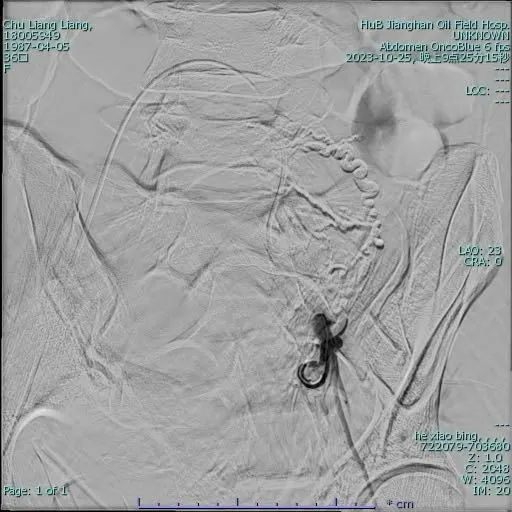

▼右侧子宫动脉栓塞手术前后▼

手术团队已提前准备。在患者推入导管室后,介入放射科主任何小兵通过DSA引导经皮穿刺股动脉将导管置入子宫动脉并释放特殊栓塞材料阻断血供成功实现了止血。

何小兵主任介绍:子宫动脉栓塞术是一种新的微创介入技术。经股动脉穿刺并置入特殊导管,注入栓塞颗粒栓塞住为子宫供血的血管以达到止血的目的,有创伤小、恢复快、并发症少、成功率高的优点。手术中用到的明胶海绵栓塞剂是半永久栓塞剂,会在栓塞血管2-4周后被人体吸收,子宫动脉就会复通,子宫血供可以恢复到栓塞之前。